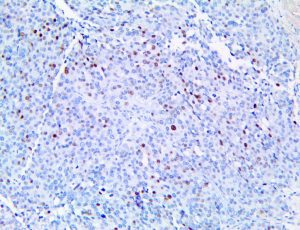

It is the ICU physician who is most likely to witness one of the deadliest manifestations of the abnormal immunological response, the cytokine storm syndrome (CSS). This response is also referred to by some as the cytokine release syndrome (CRS). CSS is characterized by continuous activation and expansion of macrophage and lymphocyte populations, which secrete large amounts of cytokines, causing the cytokine storm. This massive cytokine release is akin to hemophagocytic lymphohistiocytosis (HLH) disease, a syndrome characterized by initial unchecked and persistent activation of cytotoxic T lymphocytes and NK cells.

Clinical and laboratory manifestations of HLH include fever, enlarged liver and/or spleen, neurologic dysfunction, coagulopathy, liver dysfunction, cytopenias (i.e., low levels of erythrocytes, leukocytes, and/or platelets), hypertriglyceridemia, hyperferritinemia, hemophagocytosis, and eventually diminished NK cell activity as the immune system becomes progressively paralyzed. HLH can be familial (primary HLH) or secondary to another disease process (sHLH), such as rheumatic disease, in which it is referred to as macrophage activation syndrome (MAS, characterized by elevated ferritin).